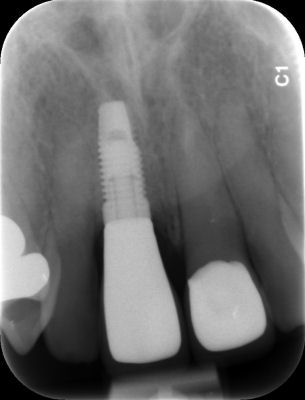

Implants have been around for many years and are a predictable method to replace missing teeth. They offer a way to have artificial teeth that look natural and feel secure. An oral implant is a titanium screw that is embedded into the jaw bone. Bone heals very tightly against the implant making the implant fixed to your jaw.

An implant replaces the root of the tooth to support a false tooth (implant crown). The dental surgeon, usually a Periodontist (gum specialist) or an Oral Surgeon, places the implant into a hole made in the jawbone during surgery. A post (abutment) is then be secured onto the top of the implant to secure the crown.

A surgical procedure is required to place the implant into your jaw bone. This procedure is uncomfortable but not painful. Local anaesthetic solution is administered to the operative site and this can be combined with oral or intravenous sedation depending on your needs. It is crucial that there is enough bone height and width to be able to place the implant with predictable results.

Sometimes if there is insufficient bone height remaining, the final appearance of an implant crown may not be perfect. You will be advised on whether an implant is the most suitable option for you and what the expected result should be like. Extra surgical procedures such as grafting may need to be required if there is insufficient bone to place the implant.

It is important that you understand that implant restorations consist of two parts, the titanium implant and the implant crown. Research has demonstrated that dental implants may remain integrated with bone in excess of 25 years and many implants will remain integrated for life. The limiting factor for the survival of implant restorations is usually the implant crown. Maintenance issues that may occur with the implant crown include fracture of porcelain or the framework, screw loosening, screw fracture and loss of the filling within the screw access hole.